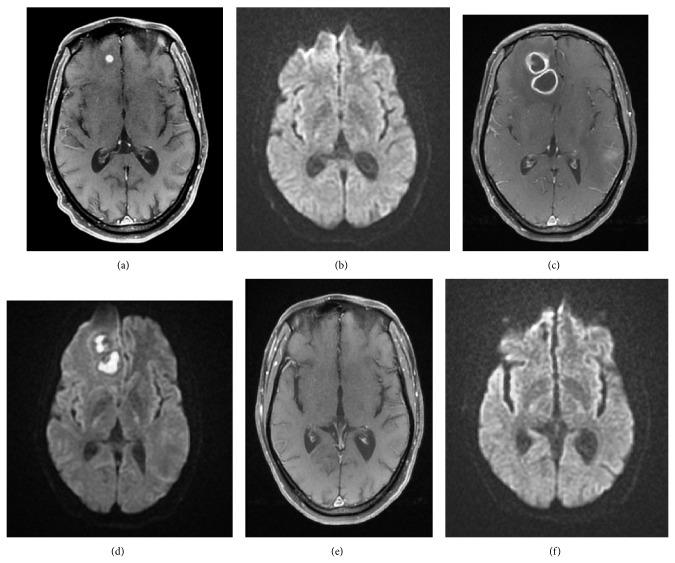

Background. Nocardiosis is a rare disease that mainly affects severely immunocompromised patients. Symptoms are nonspecific and microbiological isolation is difficult, hiding the diagnosis. Treatment should be guided by species and susceptibility testing. Findings. We report a clinical case of a disseminated nocardiosis in a patient with HIV and HVB infections. Interpretation. Diagnosis should be presumed early and microbiological conditions should be optimized, in order to identify the species and achieve antibiotic susceptibility testing. This is a very important step to choose an effective therapeutic regimen or alternative options.